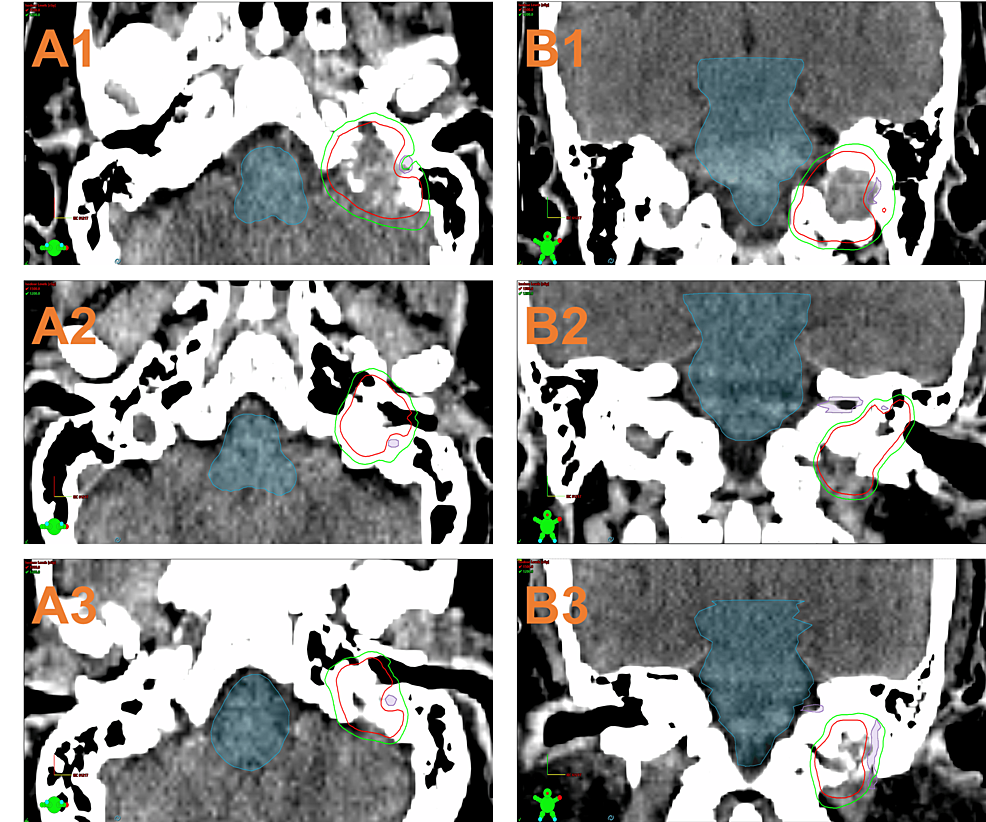

Contrastenhanced 3D images of a glomus jugulare tumor with

Contrastenhanced 3D images of a glomus jugulare tumor with Glomus Jugulare Radiosurgery Glomus jugulare tumors (gjts) are benign paragangliomas of the jugular foramen. Glomus jugulare tumors (gjts) are challenging to treat due to their vascularization and location. Because of its high effectiveness, we suggest considering radiosurgery for the primary management of glomus jugulare. Traditional management of these tumors. Gamma knife radiosurgery is a safe and effective primary therapy and salvage therapy for. Glomus Jugulare Radiosurgery.